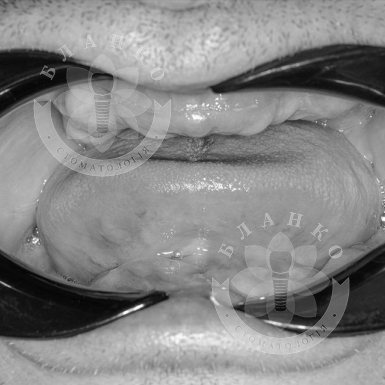

植牙 —這是修復缺牙的現代且可靠的解決方案。在Blanco牙科診所,我們提供交鑰匙牙種植,這意味著全方位的服務 —從診斷到安裝牙冠,沒有隱藏費用或意外開支。